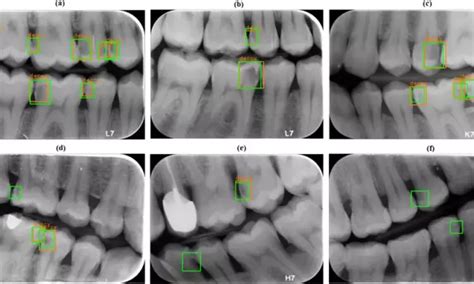

AI-assisted bitewing radiographs have high accuracy for caries ...

Artificial intelligence may help detect proximal caries on bitewing x ...

AI systems promising for diagnosis of dental caries on intraoral ...

Detecting Proximal Caries on Periapical Radiographs Using Convolutional ...

AI-Enabled Smartphone App for Caries Detection on Bitewing Radiographs ...